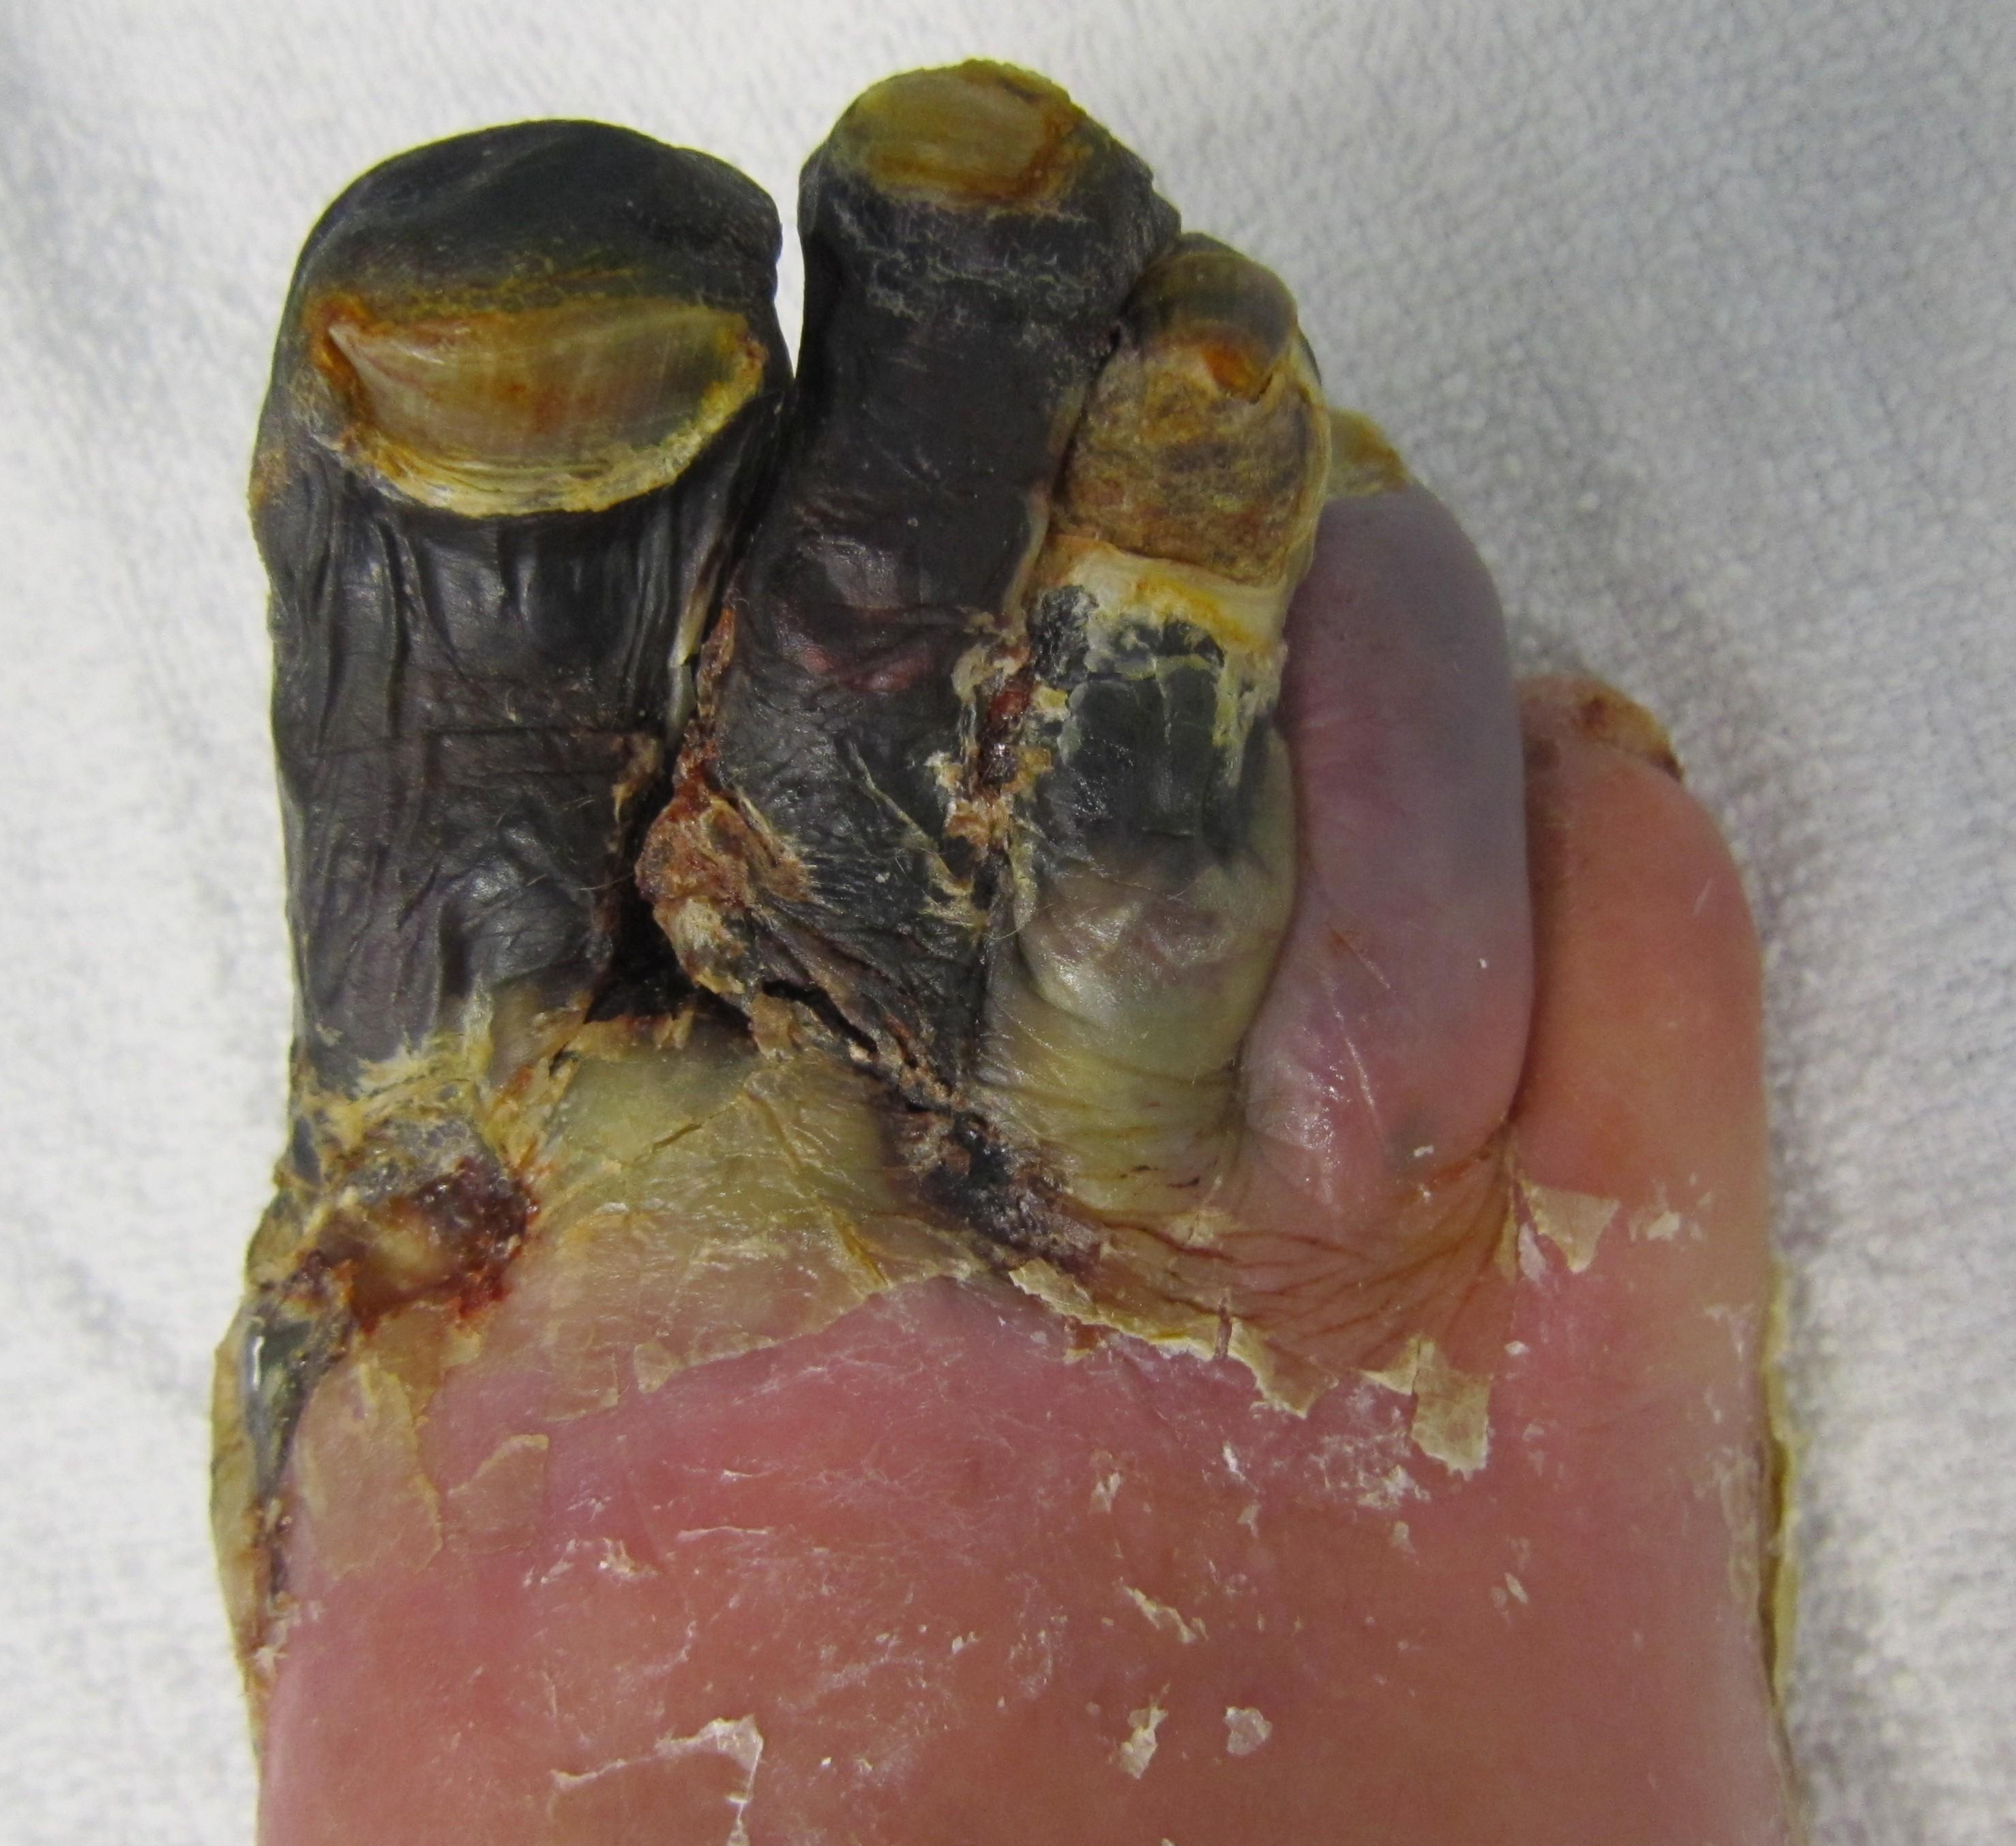

坏疽

(gangrene、gangrenous necrosis)是指因感染、血栓或其他原因缺乏血液循环造成身体组织坏死和腐烂的症状。

分类干性坏疽:常见为肢端组织缺血坏死,干枯变黑并向躯干发展,直到血液循环足以防止坏死的地方停止。干性坏疽的病变界线清楚。早期干性坏疽的症状为患处表面发白,感觉钝痛和冷。在这个阶段局部改善循环有治愈的可能,其后则需要去除坏死组织。但不经处理的话,最终坏死部分也会自行脱落。湿性坏疽:局部软组织糜烂,形成浅位溃疡。溃疡进一步向下发展,深入肌肉甚至骨质。内部坏疽是泛指出现在身体内部(而不是肢端或体表)的坏疽。例如生长过快的恶性肿瘤可能切断其内部血液供应形成坏疽;内脏由于感染(阑尾炎)或机械性疾病(肠套叠)等也可能导致坏疽。气性坏疽:见于气性坏疽杆菌侵入外伤伤口引起,发展很快而且后果严重,可有气体或无气体产生。潜伏期6小时-6日,临床症状为胀裂样剧痛,伤口开始红肿,皮肤苍白,紧张发亮。随后伤处转紫黑色,出现有暗红液体的水泡,并且可流出恶臭液体。伤口内肌肉暗红肿胀,失去弹性,刀割不收缩亦不出血。后期出...